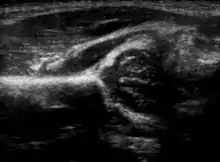

Дисплазія кульшового суглоба, діагностована за допомогою УЗД[41] та проекційної рентгенографії («рентген»)[42]. Зазвичай ультразвукова візуалізація є бажаною до 4 місяців через обмежене окостеніння скелета[40][notes 1].